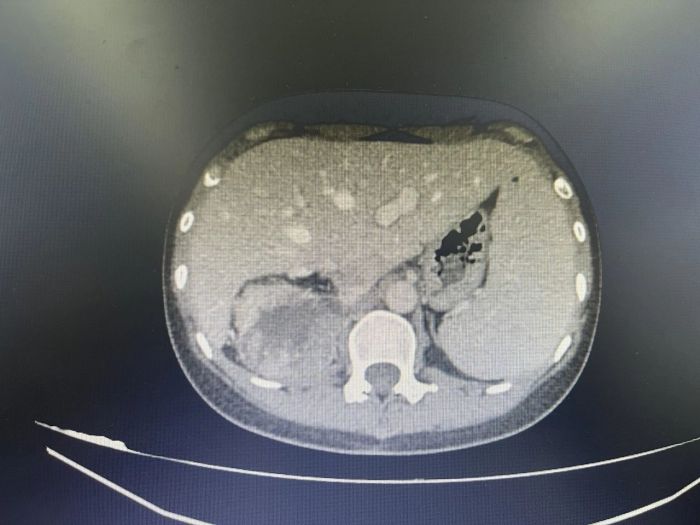

申智勇博士门诊详细了解了陈女士的病情后,结合科室此前多次成功案例,决定采用术前新辅助靶免治疗后再进行手术的方法,遂安排患者入院。后经过进一步相关检查,提示右肾占位,肾恶性肿瘤可能性大,局部肾周粘连严重,肝下缘与肿瘤无明显界限,肾门淋巴结肿大并融合,与右肾静脉、右肾动脉分界不清,进一步行“经皮肾肿瘤穿刺活检术”后,病理结果回示:符合肾透明细胞肾细胞癌。

靶向联合免疫治疗前